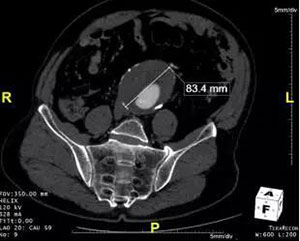

该患者为老年男性,腹主动脉瘤最大直径大于7cm(图1,图2),属于巨大腹主动脉瘤,如不及时处理,随时有发生破裂致猝死的可能。该患者既往高血压病史20余年,冠心病病史10余年,同时合并冠脉多支病变,脑梗塞病史2年,合并病多,不能耐受传统的开放手术,进行腹主动脉瘤切除+人工血管重建术;而该患者如行腔内治疗,近端肾下锚定区长度不足,传统情况下,此类患者一般会无法进行有效治疗,无奈等待破裂死亡。该患者曾于外院诊治,外院均无处理腹主动脉瘤的方法。

图1